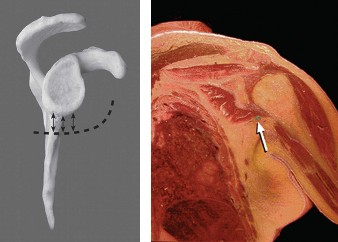

A 17-year-old gymnast presents to clinic with right shoulder pain. She denies any specific injury but reports…